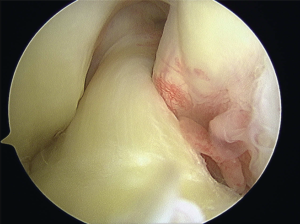

Reconstruction involves placing a graft inside the knee by arthroscopic surgery (keyhole). A

>90% success rate is normal with some deterioration over time depending upon other damage within the joint.

In the surgery a graft will be harvested to use to reconstruct the torn ligament. Usually two of the hamstring tendons are taken, but sometimes other suitable graft choices are used. This will be discussed with you prior to the operation. The remnants of the torn ACL are removed with keyhole surgery and tunnels are made in the tibia (shin bone) and femur (thigh bone) to allow the graft to be positioned across the knee. The new reconstructed ligament is then fixed at both ends to secure it in place.

Anatomical ACL reconstruction

Anatomic placement of an anterior cruciate ligament (ACL) graft is critical

to the success and clinical outcome of ACL reconstruction. Anatomic ACL graft placement is defined as positioning the ACL femoral and tibial bone tunnels at the center of the native ACL femoral and tibial attachment sites.

Clinical studies have demonstrated that non-anatomic ACL graft placement is the most common technical error leading to recurrent instability following ACL reconstruction.